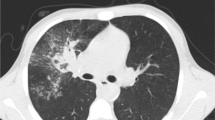

After more than 170 years, the state of preservation of Frederic Chopin’s heart is still excellent. It fills about ¾ of the jar’s volume; the overall appearance clearly indicates a significant hypertrophy of the organ. The heart is incomplete; several anatomical structures are missing: the left atrium and most of the right atrium together with blood vessels, except for the so-called right auricula, the trunks of the main artery, and the pulmonary artery. The color of the myocardium is typical of fixed muscle.

The general heart appearance corresponds to the morphological features of cor pulmonale, with significant enlargement of the right ventricle; the left ventricle is enlarged to a lesser extent. In the anterior wall of the left ventricle, a long dissection incision is visible, which allowed an insight into its lumen and an assessment of its interior and the condition of the mitral valve; the incision was stitched with several surgical sutures. Previously, little attention was paid to a postmortem examination of the right heart, which by today’s criteria presents a deviation from the proper autopsy technique. Right ventricular hypertension, a consequence of pulmonary hypertension, has led to a right ventricular myocardial hypertrophy and dilatation, most likely accompanied by a right atrial hypertension, hypertrophy of its walls, and/or dilatation. Such a hypertrophy of the myocardium (hypertrophia cordis) results in extensive changes in the myocardium: altered myocyte thickness and length, decreased capillary density, increase in connective tissue with no systolic function, increased metabolic requirements, which altogether lead to increased vulnerability to decompensation. Such extensive cardiomegaly is usually accompanied by symptoms of myocardial failure. The appearance of Chopin’s heart suggests its chronic, mainly right ventricular, failure.

The lack of vessels of corona cordis (aorta and pulmonary trunk) and the absence of atria may be explained by the postmortem technique used in France and the satellite countries, differing from the “German-Austrian”; the previous involves cutting off the heart from the rest of thoracic organs at the level of corona cordis and examining it separately. In the “German” technique, the whole set of organs (heart, lungs, esophagus) is removed from the chest and then each of them is examined separately (Dérobert 1974; Piédelièvre and Fournier 1963). Because Chopin’s heart was enlarged and flaccid at the time of the autopsy, the incision was overly low, leading to damage of both atria. Hemorrhagic effusions, probably as a result of the presence of a subendocardial bloody fluid typical of tuberculous pericarditis, were clearly visible, mainly on a wall of the left ventricle.